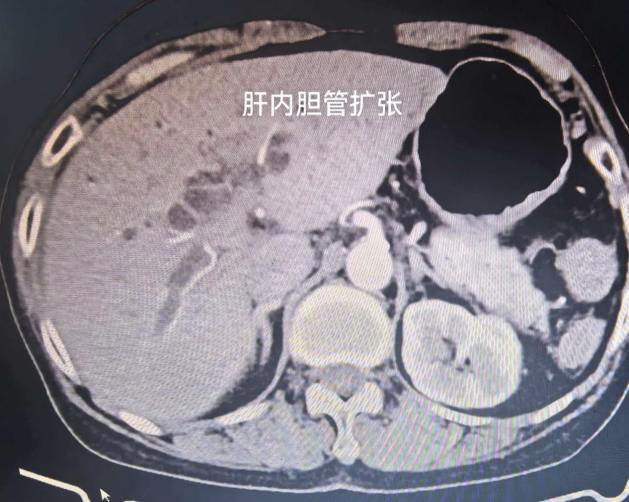

肝胆外科副主任周新红接诊后,敏锐判断病情危重,立即安排上腹部增强CT及磁共振检查。结果显示,患者胆总管下段及胰腺段存在肿瘤性病变,已导致胆道严重梗阻。